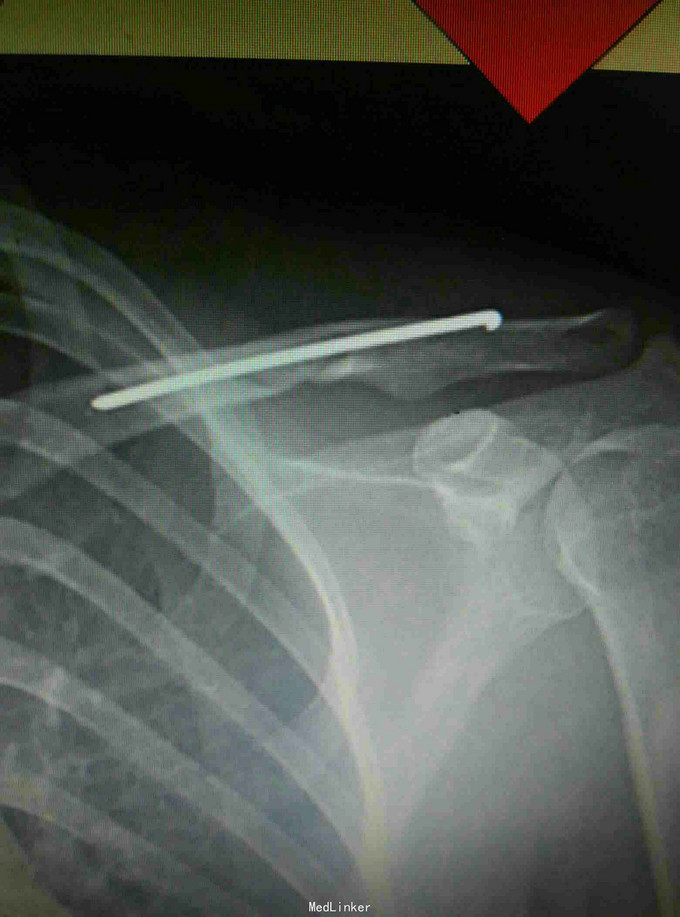

诊断:左锁骨骨折。 给予行闭合复位钢针固定。

术后恢复良好,术后4个月门诊拔除钢针。 讨论:锁骨骨折是临床常见的骨伤科疾病之一,骨折多发生在锁骨,一般通过手法整复,8字绷带固定,三角巾悬吊可以活的良好的效果,但也经常出现不愈合,畸形愈合等情况,如果采用钢板固定,存在过度治疗,影响美观,需再次手术取出等不足,我们采用闭合复位钢针固定,创伤小,不影响美观,可门诊直接拔除钢针,无需二次住院。